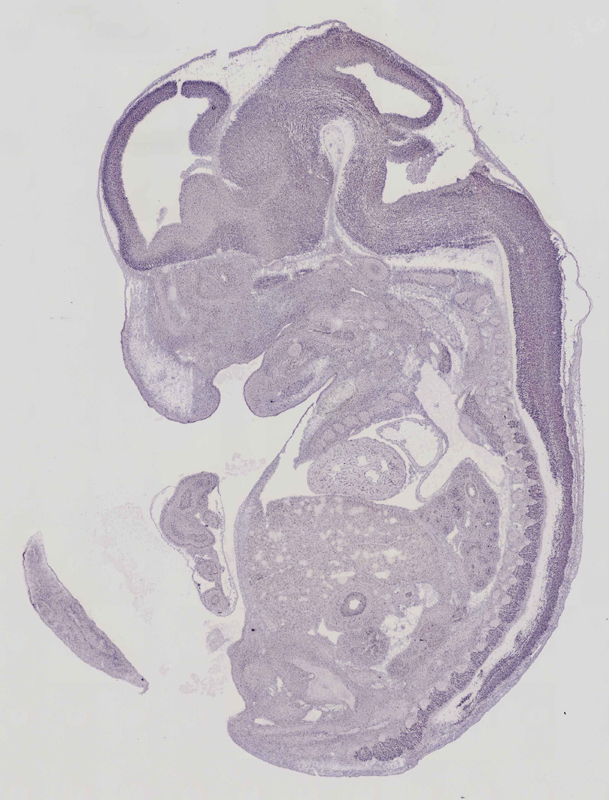

Specimen euxassay_006621_03: embryonic day 14.5 (more )

Structure Level Pattern Image Note

TS23: trigeminal ganglion Moderate Regionally restricted euxassay_006621_03

Specimen euxassay_006621_04: embryonic day 14.5 (more )

TS23: trigeminal ganglion Moderate Regionally restricted euxassay_006621_04

TS23: facial ganglion Moderate Regionally restricted euxassay_006621_04